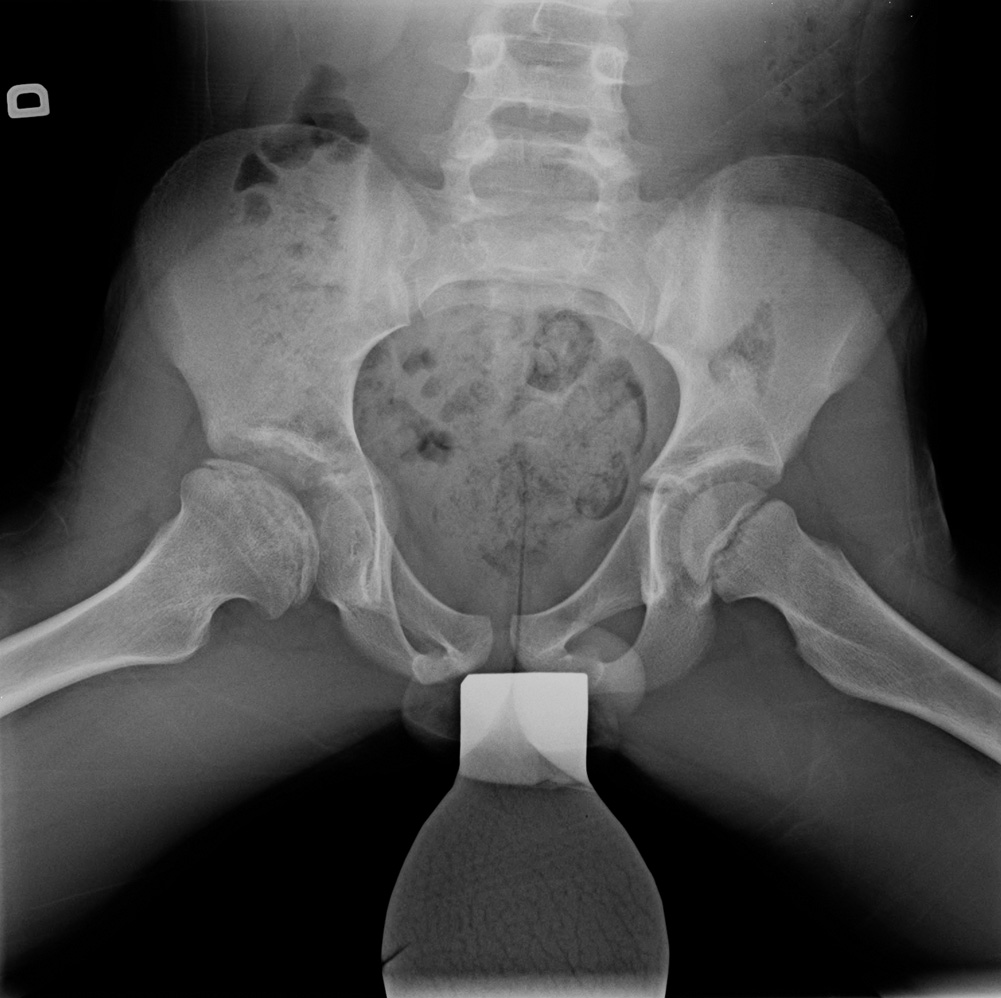

9-year-old male:

Follow-up of a Legg-Calvé-Perthes disease.

Legg-Calvé-Perthes disease

Bony irregularities

Slight progression of the femoral head ossification compared with the previous study.

Femoral head subluxation

We can see that the right femoral head is not fully covered by the acetabular rim on the right side as opposed to the left side.

Anteroposterior